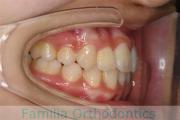

No.14V-516

- 上顎前突

- 叢生

- 10歳

- 女性

- 上:

- 44

- 下:

- 55

- 主な使用装置:

- FEA

- 治療にかかった費用:

- 90万円

きれいな歯並びにしたいということで来院されました。第一期治療で六歳臼歯の位置を維持する装置を入れて第二期治療の準備をしました。第二期は中学生になってから小臼歯を抜歯して行いました。二期治療は約2年半、25回程度の通院が必要でした。

- ≫治療中 ステップ1

二期治療開始前は叢生(でこぼこ、凹凸、ガタガタ)がかなりありましたので、保定をしっかりしないと段差ができてきたり後戻りのリスクがあります。